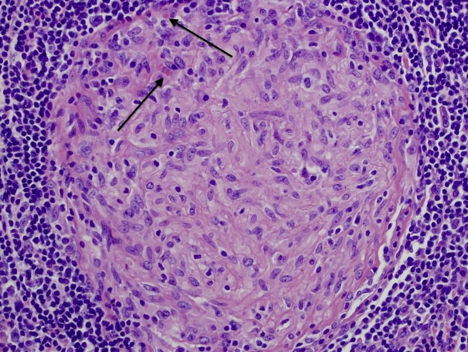

Chest wall osteosarcoma

Characteristic Histology:

Malignant spindle cells

Mitoses

Excess ostoid